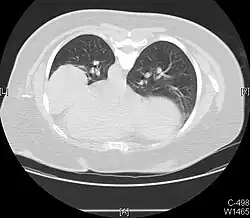

Masses

.jpg)

Masses such as tumors can also cause compression and displacement of mediastinal structures. There are various mediastinal tumors, and they are classified by their location in the chest. Notable examples include germ cell tumors and lymphomas.[12] Teratomas are a class of germ cell tumors that arise in the chest due to failure of germ cell migration during development. They can expand to large sizes and cause hemoptysis and pleural effusion. Radiographic features of teratomas typically include fluid and fat but also muscle, teeth, and bones inside the mass.[13]